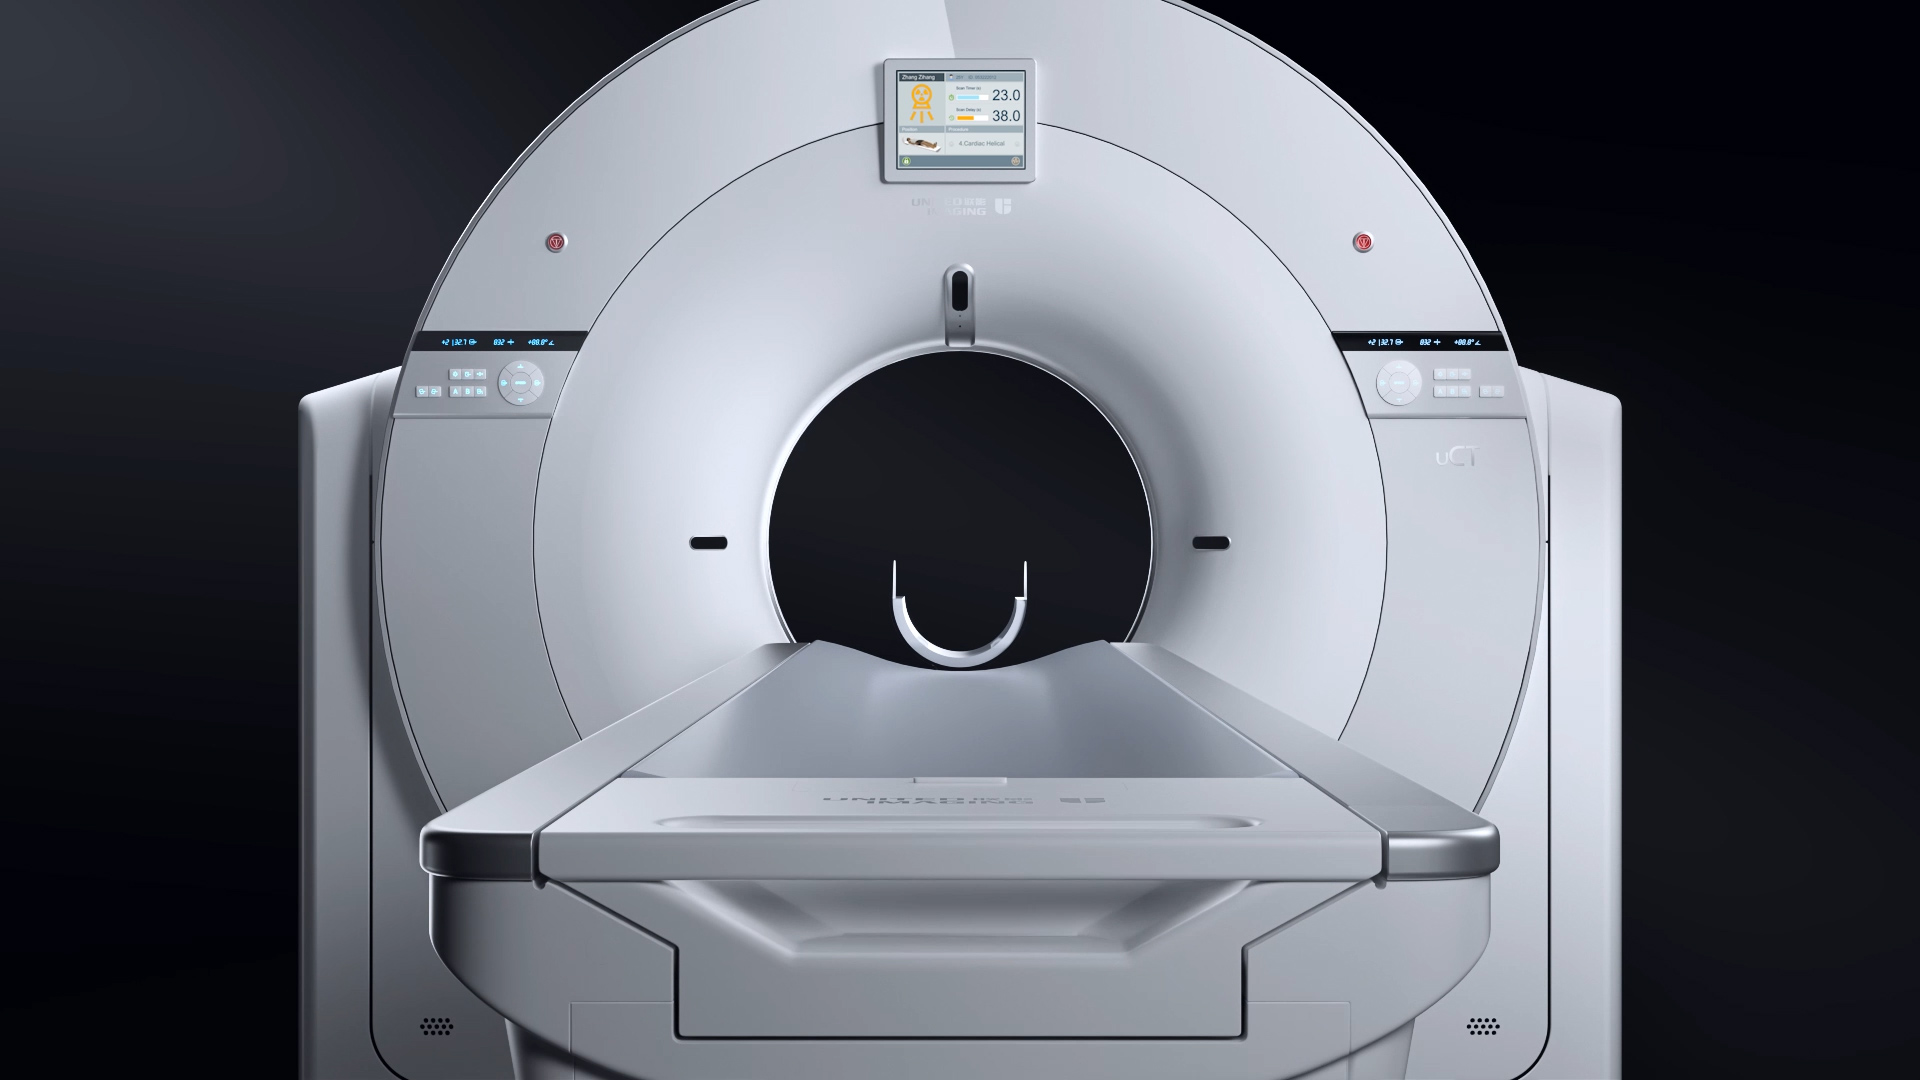

精准尽显·高效卓越

uCT 780 依托0.5mm切割的80排160层时空影像链,从数据源头提升图像质量,大幅提高早期微小病灶检出率,助力肿瘤早筛早诊;以0.3s超快转速,结合智能冠脉最佳时相算法(ePhase) ,突破高心率扫描限制,高清呈现细微结构,实现冠脉血管的精准成像。

精准图像重建,清晰显示微小病灶

0.5mm薄层扫描结合百万矩阵

精准剂量,有效降低辐射剂量与对比剂用量

70kV双低扫描技术

100kW系统最大功率,轻松应对高BMI受检者检查